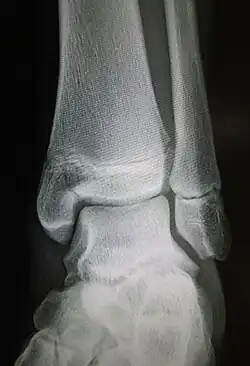

Ankle radiographs are used to detect widening of the tibiofibular syndesmosis or medial clear space. The medial clear space is the area between the talus of the ankle and the medial malleolus. Damage to the deltoid ligament and syndesmotic ligaments result in mortise instability, causing the talus to laterally shift and widen the medial clear space.[4][12] A clinical study, conducted in 2006 and published in the Journal of Bone and Joint Surgery, found that the medial clear space size of a normal ankle and an injured ankle measured at 4 millimetres and 5.4 millimetres in length respectively.[11] To confirm diagnosis, full-leg radiographs are used to inspect for fractures of the proximal fibula and widening of the interosseous clear space (or tibiofibular clear space). The interosseous clear space is the area between the medial side of the fibula and lateral side of the tibia. A peer-reviewed study, published in Injury in 2004, found that an interosseous clear space greater than 10 millimetres indicates diastasis of the syndesmotic ligaments.[4]

If necessary, computed tomography (CT) or magnetic resonance imaging (MRI) may also be used to clarify diagnosis. MRI scans can check for interosseous membrane or tibial tubercle damage if high instability of the ankle is diagnosed.[8][11] Arthroscopy may be used to diagnose a syndesmotic lesion but is often not recommended due to operative difficulty.[13] Stress radiographs of the ankle are used to assess the integrity of the deltoid ligament and tibiofibular syndesmosis.[9][13] The size of the medial clear space can also be measured using stress radiography.[11]